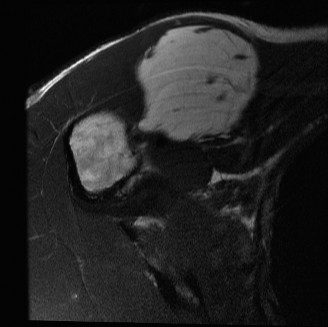

- Image Integration: The gross appearance often shows a yellow, lobulated mass, sometimes with areas of fibrosis or myxoid change, or septations. The image below depicts such a presentation, which can be seen upon initial exposure or after deeper dissection: